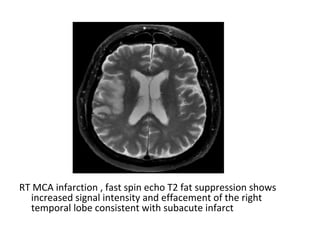

RT MCA infarction , fast spin echo T2 fat suppression shows

increased signal intensity and effacement of the right

temporal lobe consistent with subacute infarct